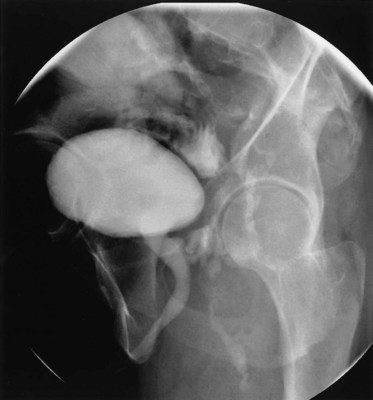

Vesicovaginal fistulae (VVF) are the most common acquired fistula of the urinary tract (Gerber and Schoenberg, 1993) and have been known since ancient times (Fig. 77–1). However, it was not until 1663 that Hendrik von Roonhuyse first described surgical repair of VVF by denuding the fistula margins and then reapproximating them with sharpened stiff swan quills (Margolis and Mercer, 1994). Johann Fatio is generally credited with the first successful VVF repair, in 1675, using von Roonhuyse’s technique (Falk and Tancer, 1954). In 1838, using leaden suture, John Peter Mettauer was the first U.S. surgeon to claim a successful VVF closure (Kight, 1967). In 1852, James Marion Sims published his now famous surgical series describing his method of surgical treatment of VVF using silver wire in a transvaginal approach (Sims, 1852). Of note, it was not until his 30th attempt at closure of VVF that he achieved success. However, Sims remains the subject of considerable debate regarding his ethics (Richardson, 1994; Sartin, 2004), because it is unknown whether the patients in his surgical series were willing and consenting participants (all were African-American slaves in pre–Civil War America). He was later to become one of the great figures in the history of operative gynecology. The first successful transabdominal approach to VVF repair was reported by Trendelenburg in 1888, and the concept of an interpositional flap was first proposed and reported in 1928 by Martius, who used a labial fat pad.

Figure 77–1 Voiding cystourethrogram demonstrates filling of the vagina with voiding due to a post-hysterectomy vesicovaginal fistula.